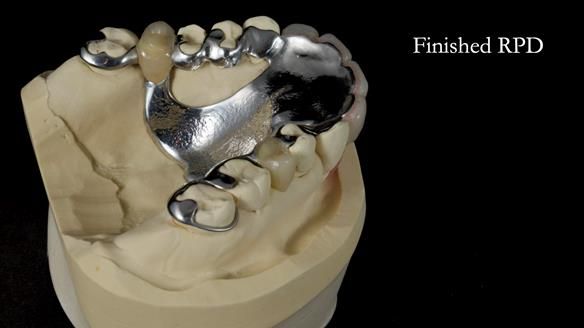

This is one of those cases that reminds me why I love removable prosthodontics. Pam was an absolute joy to treat — we were on the same page throughout. Her old upper flexible denture was loose, uncomfortable, and unaesthetic. We replaced it with a carefully designed metal-based upper partial denture/splint and new porcelain-bonded-to-zirconia (PBZ) crowns for the canines. The result is stable, comfortable, and natural-looking.

Huge thanks to Rowan Garstang (master technician), Chris Hesketh (metalwork technician), and Claire (my brilliant dental nurse) — their skill, care, and teamwork made this case possible.

- Diagnosis and plan – Flexible upper denture ill-fitting with poor stability, retention, and appearance. Plan: metal-based upper partial denture/splint with lighter porcelain-bonded-to-zirconia crowns on UR3 and UL3.

- Metalwork framework try-in – to verify fit, path of insertion, and support.